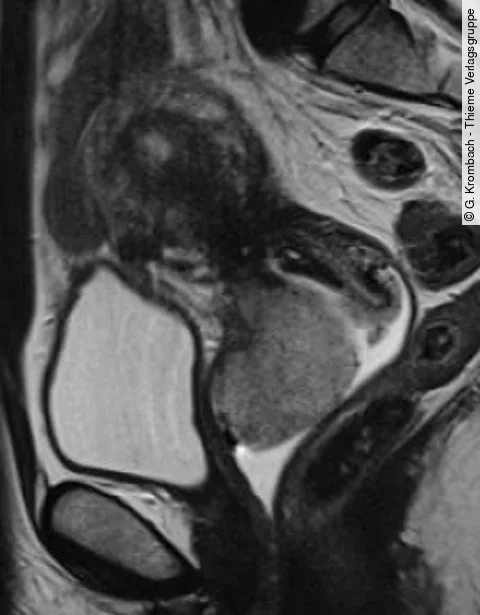

Multiple Choice QuizFIGO-Staging: Welches Stadium sehen Sie hier?

Begutachten Sie die T2w-gewichteten MRT-Aufnahmen sowie das kontrastmittelgestützte CT in der Bildergalerie.